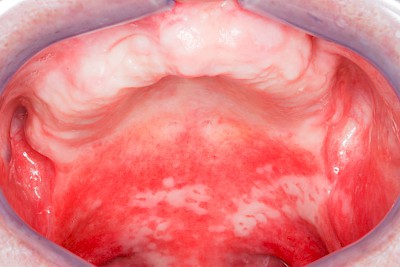

Rötung, Blutung, Verletzung

Gaumen, Wange & Zunge

Rötungen sind grundsätzlich als Anzeichen einer Entzündung zu werten.

Die 5 klassischen Entzündungszeichen:

- Rötung (Rubor)

- Schmerzen (Dolor)

- Schwellung (Tumor)

- Wärme (Calor)

- gestörte Funktion (Functio laesa)